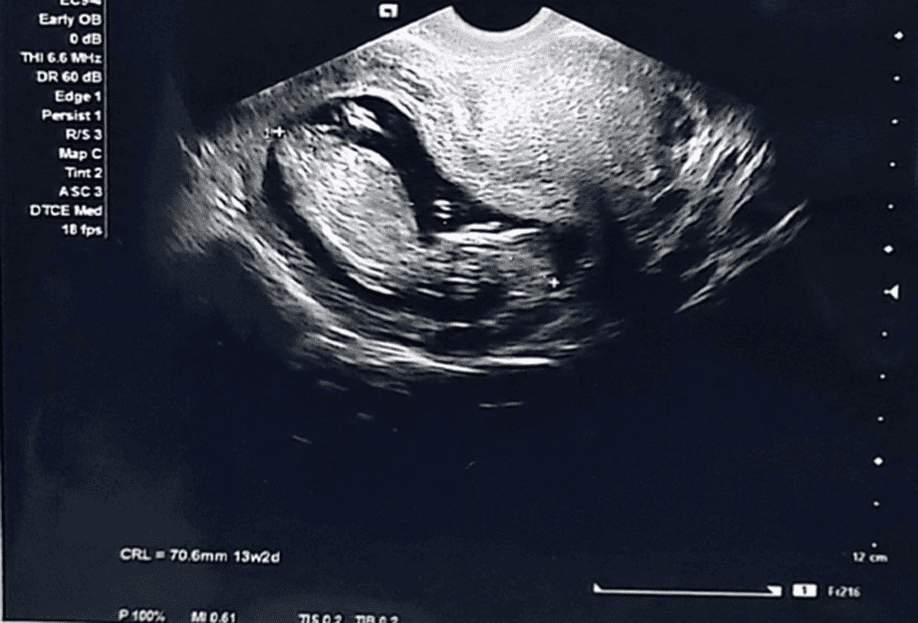

28-year-old female G7P3+0+3+3 12+4 weeks of gestation previously healthy with no known medical or surgical history presented to the outpatient department for her regular antenatal follow up. During her first visit she mentioned that she is having difficulties in passing urine. Baseline investigations including complete blood count (CBC), renal function test (RFT), urine routine and culture were done to look for urinary tract infection which was ruled out. However, the patient was given an ultrasound appointment to look for any underlying urinary tract pathology along with urology outpatient clinical referral. However, patient came after few days with worsening symptoms leading to complete urinary retention thus the patient admitted to the hospital and Foleys catheter was inserted. Our differential diagnosis was the following: Urinary tract infection, Urinary tract obstruction attributed to a urological cause i.e. nephrolithiasis or attributed to a gynecological cause i.e. large uterine fibroid. During hospital stay urine culture was repeated which came back with no growth. An Ultrasound was done by an obstetrician which revealed an acutely retroverted uterus with a fetus matching gestational age calculated from the first day of her last menstrual period (LMP) as shown in Figure 1 and 2.

Figure 1: Transvaginal ultrasound revealing an acutely retroverted uterus with a picture of uterine incarceration

Figure 2: Transvaginal ultrasound revealing an acutely retroverted incarcerated uterus with a viable fetus matching 12 weeks of gestation